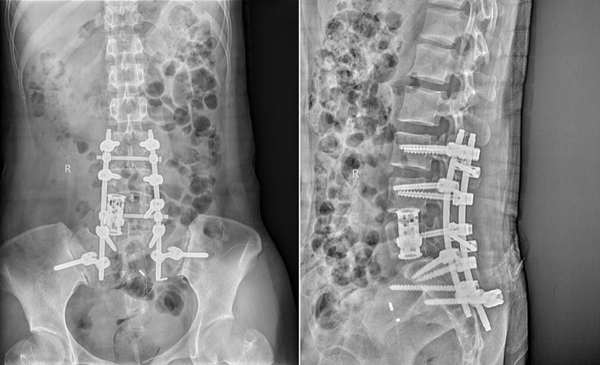

2022年6月13日,党晓谦主任、樊立宏教授带领团队在麻醉科吴刚、赵亚琴团队、普通外科马建仓教授、神经外科王睿智教授、肿瘤病院张寅斌教授及手术室护士的协助下,为患者顺利施行前后联合入路腰椎肿瘤切除人工椎体重建钉棒内固定术。首先,经后入路行L4、L5全椎板减压,术中探查见肿瘤组织包绕、粘连右侧L5神经根近端,约5cm×3cm大小,肿瘤向前内侵蚀L5椎体右侧部分骨质并延伸至腹膜后,与周围组织粘连紧密。后路彻底清除瘤体后残余部分推入前方待从前入路切除,后于L4-S1右侧植入可调式人工椎体并钉棒固定。之后更换体位,于前路行倒“八”字切口逐层暴露,将瘤体与下腔静脉仔细分离完整剥离。经过10个小时的奋战,完整切除神经鞘瘤,植入可调式人工椎体,并避免损伤硬膜囊、下腔动静脉、股神经等重要结构,成功为腰5巨大神经鞘瘤患者实施肿瘤切除腰椎重建手术,术后患者规律戴支具并接受专业康复训练。

术后腰椎正侧位